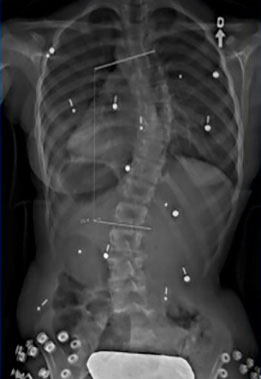

Adolescente scoliotique avant et après SpineCor®

Colonne vertébrale scoliotique d’une adolescente, avant le traitement SpineCor® et à la fin du sevrage après trois ans de port quotidien. Les radiographies démontrent une correction spectaculaire.

Colonne vertébrale de l'adolescente avant SpineCor®

Colonne vertébrale de l'adolescente avec SpineCor®